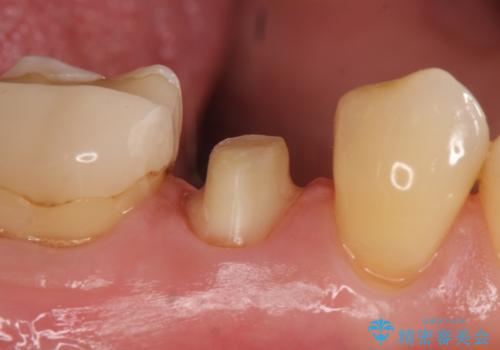

検査の結果右下5番目の歯の神経が死んでいたため、根管治療を行った後、オールセラミッククラウンによる補綴を行いました。

今回用いたオールセラミッククラウンはジルコニアフレームという白い素材の上にセラミックを盛っているため、審美性が非常に高いのが特徴です。

また、ジルコニアは人工ダイヤモンドの材料にも使われているほど高い強度を持っており、そのためオールセラミッククラウンは審美性だけでなく、奥歯やブリッジの補綴も可能とするクラウンです。